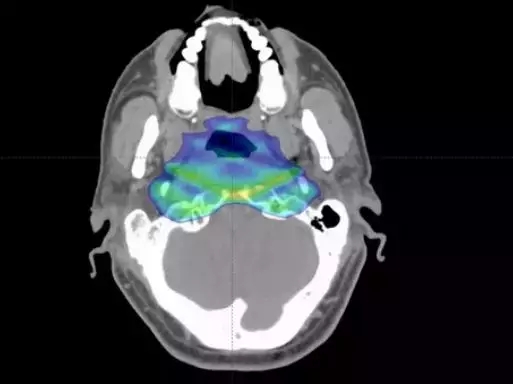

图示高辐射剂量集中于肿瘤部位,周边正常组织无/极少剂量

图注:图中强度调强质子治疗(IMPT)的辐射主要集中于鼻咽癌病灶周围,对周围正常组织的无影响或影响较小,而强度调强放射治疗(IMRT)的辐射面积较大,涵盖病灶及周围正常组织